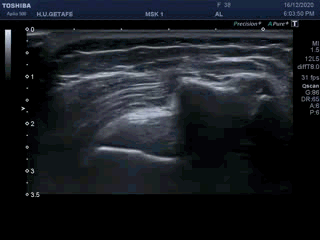

Y lo que debes ver ecográficamente es esto:

5

Una vez que tengas bien claro todos los asistentes a la fiesta, y con el movimiento del brazo del paciente, asistido por nosotros o realizado por el propio paciente, partiendo de la base de la imagen 5, superior, que acabas de estudiar, conseguirás esto en tiempo real…mira: